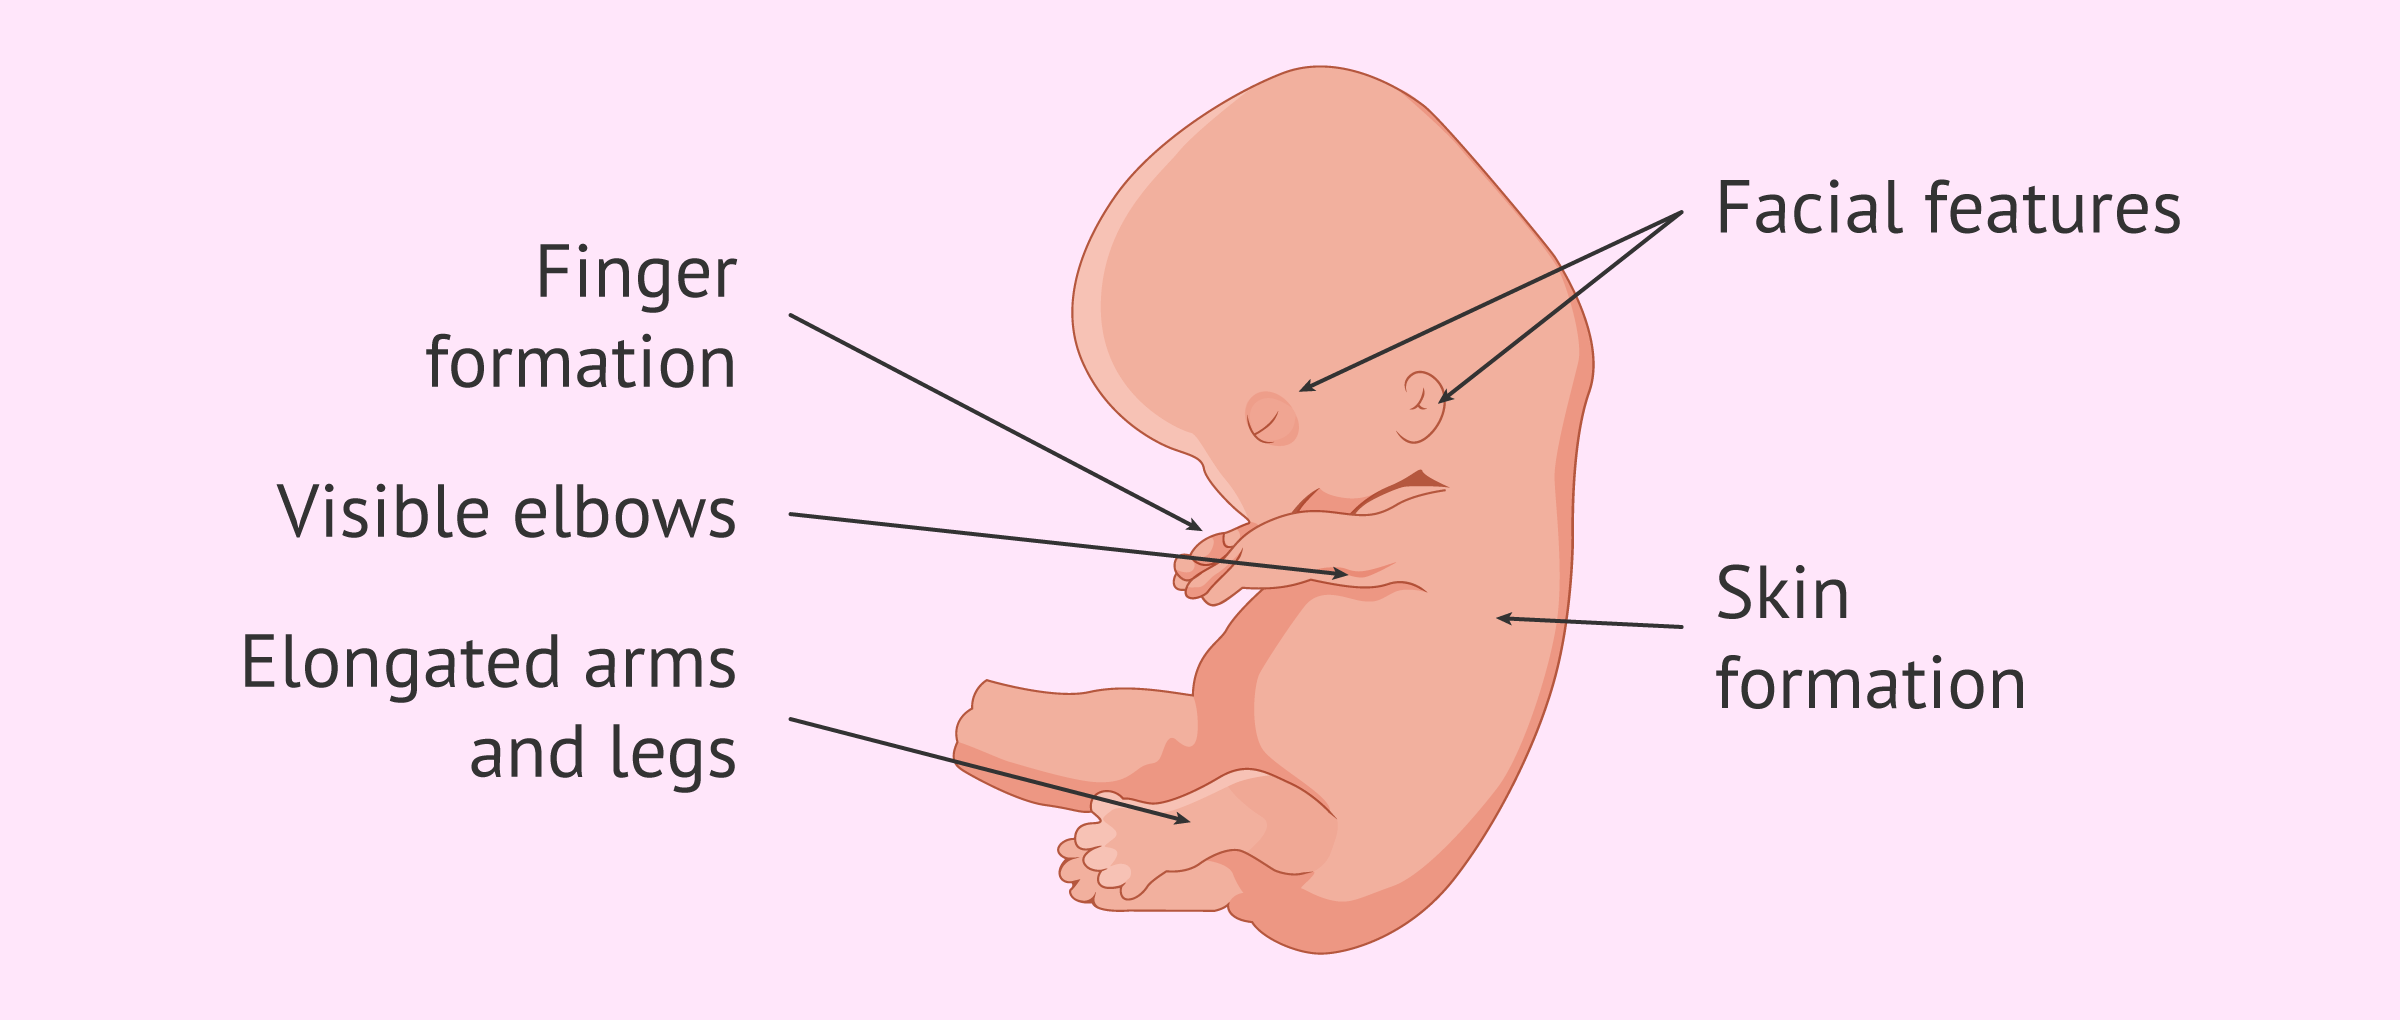

II. End of 8th Gestational Week

Length: 2.5 cm (1 in)

Weight: 20 g

Organogenesis is complete.

The heart, with a septum and valves, is beating rhythmically.

Facial features are discernible.

Arms and legs have developed.

External genitalia are forming, but sex is not yet distinguishable by simple observation.

The primitive tail is regressing.

The abdomen bulges forward because the fetal intestine is growing so rapidly.